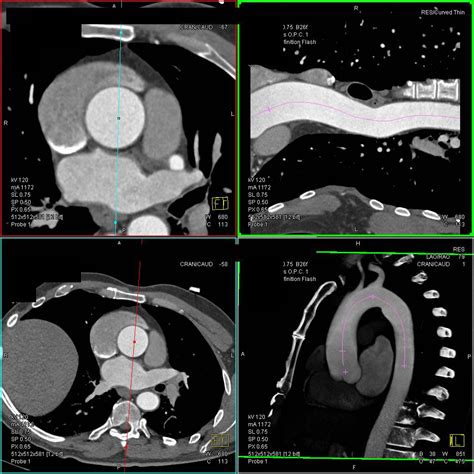

CT Angiography (CTA) Uses contrast dye to create detailed 3D images of the aorta.

Magnetic Resonance Angiography (MRA) Offers highly accurate measurements without exposure to ionizing radiation.